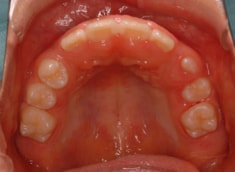

小児期ケース:反対咬合(受け口)

治療前